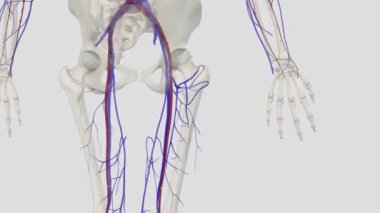

SağlıkkanİlaçkalpStetoskopTedaviHastalıkbiyolojiGöğüsorgİyileştiriyorvenanatomibelirtileriobstrüksiyonarterkapillerkasılmaAtriumGöğüs kemiğiaortKalp kriziKalp kasıGöğüs Ağrısıkalp zarınıKan damarıStentkan akımıacil tedaviKoroner artersol ventrikülSağ ventrikülkalp ilacıdiyaframdanKalp kapakçığıkardiyovasküler sistemSol atriyumPulmoner dolaşımSistemik dolaşımPulmoner arterSağ atriumsemilunar valvepulmoner venbicuspid valvepapillary musclecardiac septumcardiac wallheart catheterisationBenzer İçerikler